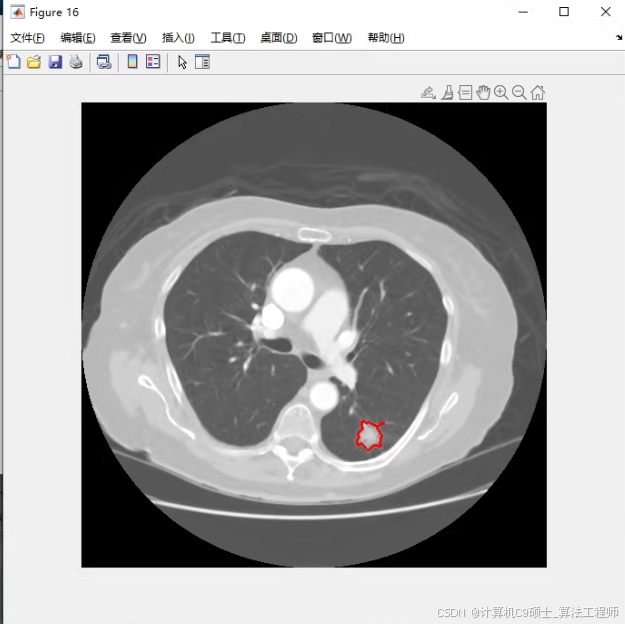

4、肺结节分割。肺质分割后,进行特征提取,计算灰度特征、形态学特征来分割出肺结节;

肺结节分割

肺结节分割:segment_nodule.m在肺质分割后,进行特征提取,计算灰度特征和形态学特征来分割出肺结节。